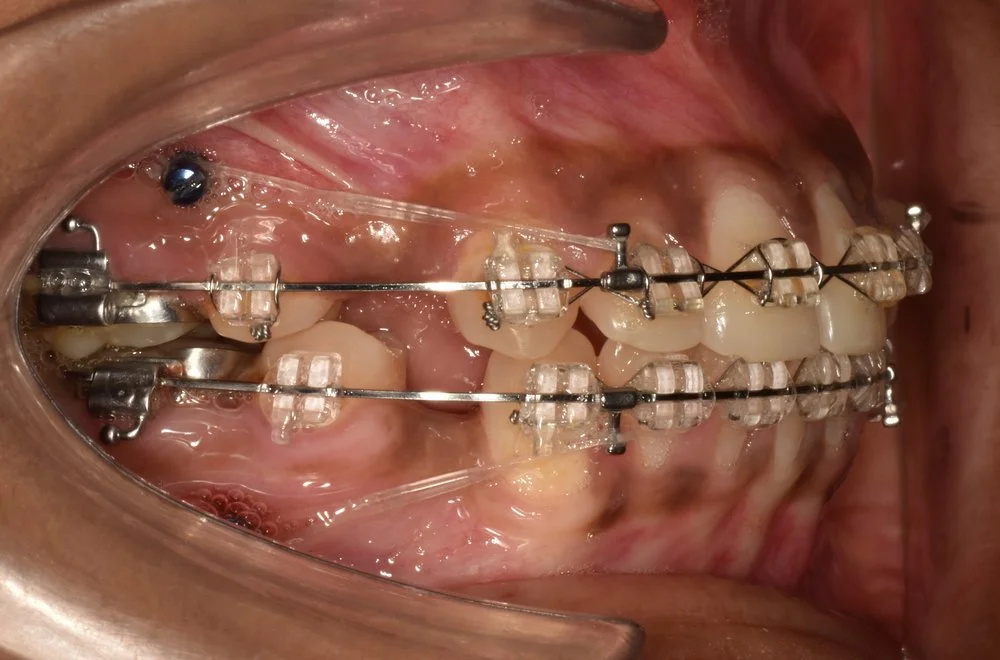

Extra-radicular implants